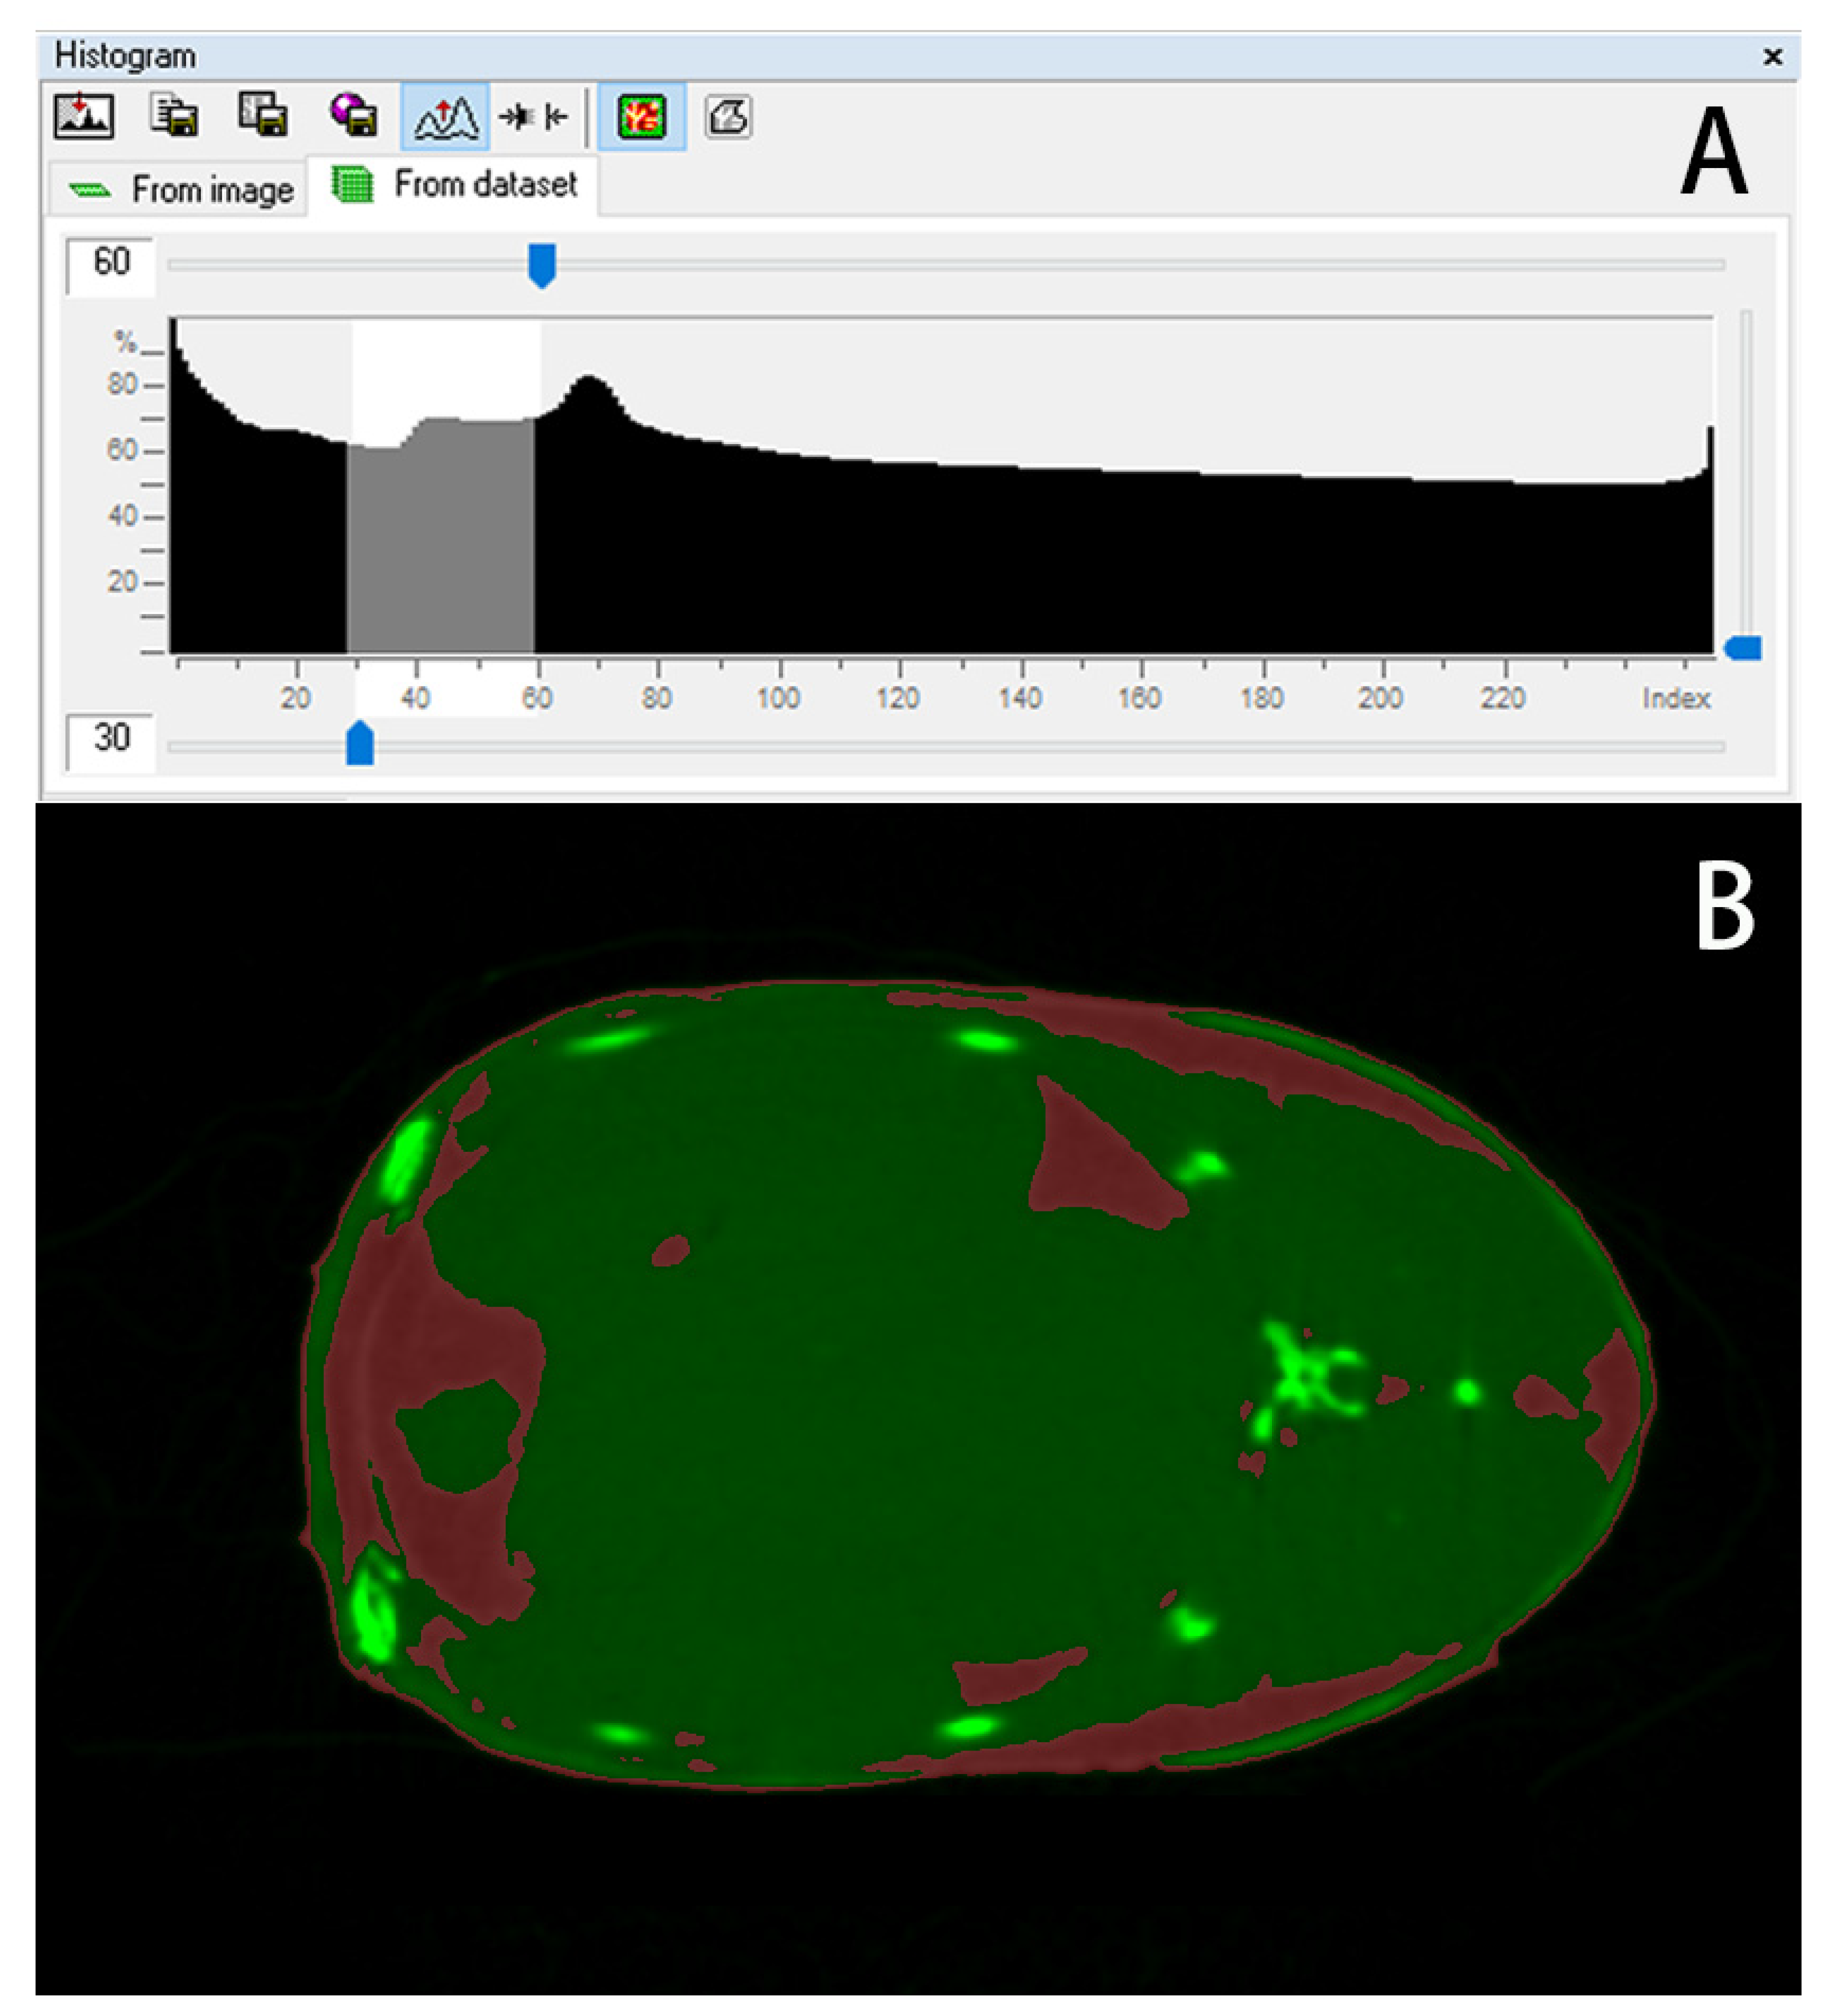

2.5. Data Processing

3.4. Quantitative Calculation of Trunk Adipose Tissue